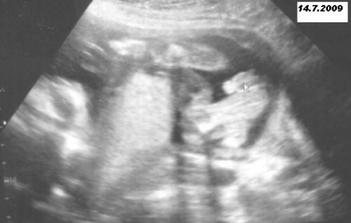

Všechny testy dopadly na jedničku a 7.7. jsme se na dalším utz dozvěděli, že čekáme chlapečka.

14.7.2009 proběhl genetický utz. a zase všechno v pohodě - huráááá.

Miminko krásně roste a mamince se zvětšuje bříško den ode dne 🙂